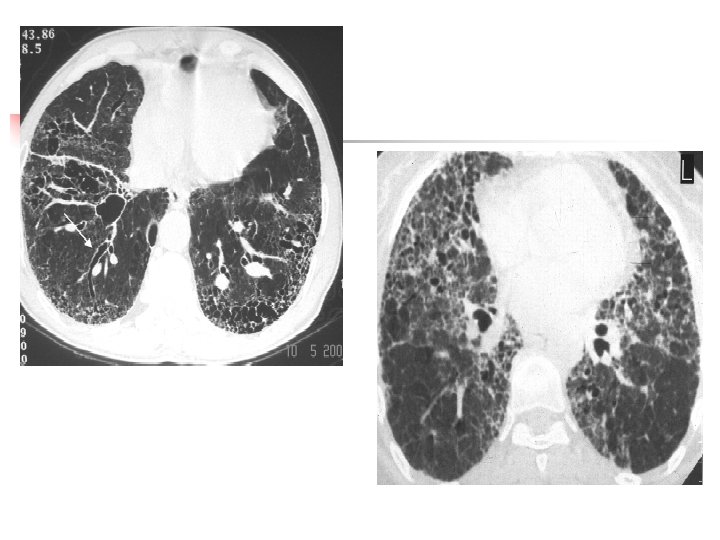

Tomodensitométrie Prédominance dans les régions supérieures et postérieurs Ø Micronodules Centrolobulaires et/ou sous pleuraux (répartition lymphatique) De 2 à 5 mm de diamétre Ø Nodules bien limités/distribués de façon homogène Ø Masse de fibrose forme ovale contours irréguliers parfois calcifiées, et/ou excavées Ø Distorsion Ø Adénopathies médiastinales/parfois calcifiées en coquille d ' oeuf

Silicose Micronodules centrolobulaireet sous pleuraux Masses de fibrose de siége central périhilaire, englobant les bronches Proximales.